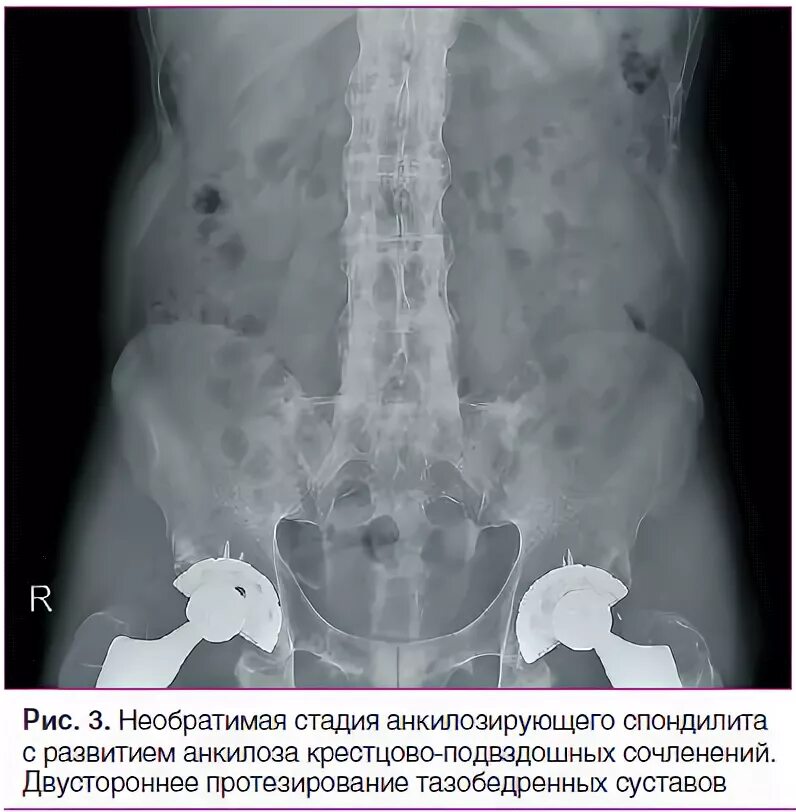

Болезнь бехтерева тазобедренных суставов